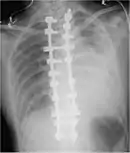

Thoracostomy

Blood in the cavity can be removed by inserting a drain (chest tube) in a procedure called a tube thoracostomy. This procedure is indicated for most causes of hemothorax, but should be avoided in aortic rupture which should be managed with immediate surgery.[30] The thoracostomy tube is usually placed between the ribs in the sixth or seventh intercostal space at the mid-axillary line.[15] It is important to avoid a chest tube becoming obstructed by clotted blood as obstruction prevents adequate drainage of the pleural space. Clotting occurs as the clotting cascade is activated when the blood leaves the blood vessels and comes into contact with the pleural surface, injured lung or chest wall, or the thoracostomy tube. Inadequate drainage may lead to a retained hemothorax, increasing the risk of infection within the pleural space (empyema) or the formation of scar tissue (fibrothorax).[31] Thoracostomy tubes with a diameter of 24–36 F (large-bore tubes) should be used, as these reduce the risk of blood clots obstructing the tube. Manual manipulation of chest tubes (referred to as milking, stripping, or tapping) is commonly performed to maintain an open tube, but no conclusive evidence has demonstrated that this improves drainage.[8] If a chest tube does become obstructed, the tube can be cleared using open or closed techniques.[32] Tubes should be removed as soon as drainage has stopped, as prolonged tube placement increases the risk of empyema.[33][6]

Surgery

About 10–20% of traumatic hemothoraces require surgical management.[6] Larger hemothoraces, or those that continue to bleed following drainage, may require surgery. This surgery may take the form of a traditional open-chest procedure (a thoracotomy), but may be performed using video-associated thoracoscopic surgery (VATS). While there is no universally accepted cutoff for the volume of blood loss required before surgery is indicated, generally accepted indications include more than 1500 mL of blood drained from a thoracostomy, bleeding rate of over 500mL/hr in the first hour followed by over 200 mL, hemodynamic instability, or the need for repeat blood transfusions.[8][6] VATS is less invasive and cheaper than an open thoracotomy, and can reduce the length of hospital stay, but a thoracotomy may be preferred when hypovolemic shock is present,[3] in order to watch bleeding.[34] The procedure should ideally be performed within 72 hours of the injury as delay may increase the risk of complications.[19] In clotted hemothorax, VATS is the generally preferred procedure to remove the clot, and is indicated if the hemothorax fills 1/3 or more of a hemithorax. The ideal time to remove a clot using VATS is at 48–96 hours, but can be attempted up to nine days after the injury.[6]